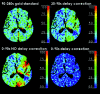

Hemorrhagic transformation is a serious potential complication of ischemic stroke with damage to the BBB as one of the contributing mechanisms. BBB permeability measurements extracted from PCT by using the Patlak model can provide a valuable assessment of the extent of BBB damage. Unfortunately, Patlak assumptions require extended PCT acquisition, increasing the risk of motion artifacts. A necessary correction is presented for obtaining accurate BBB permeability measurements from first-pass PCT.